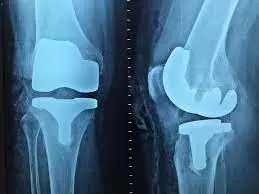

degenerativnih oboljenja (koleno, rame, kuk, stopalo)

bolnih zglobnih stanja

tretmani kolena